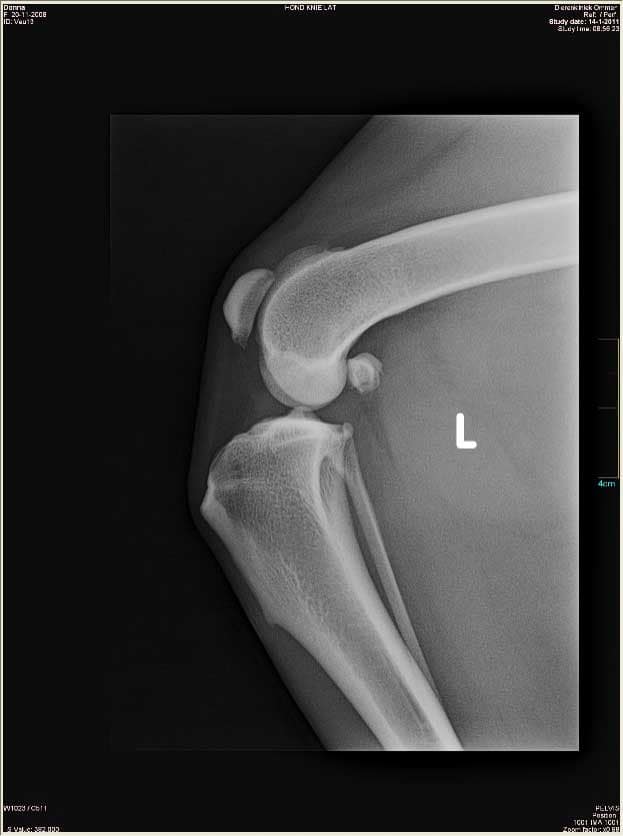

Hieronder links een foto van een gezonde knie en rechts een knie met gescheurde voorste kruisband. Hierbij valt op dat het onderbeen naar voren is geschoven bij de zieke knie.